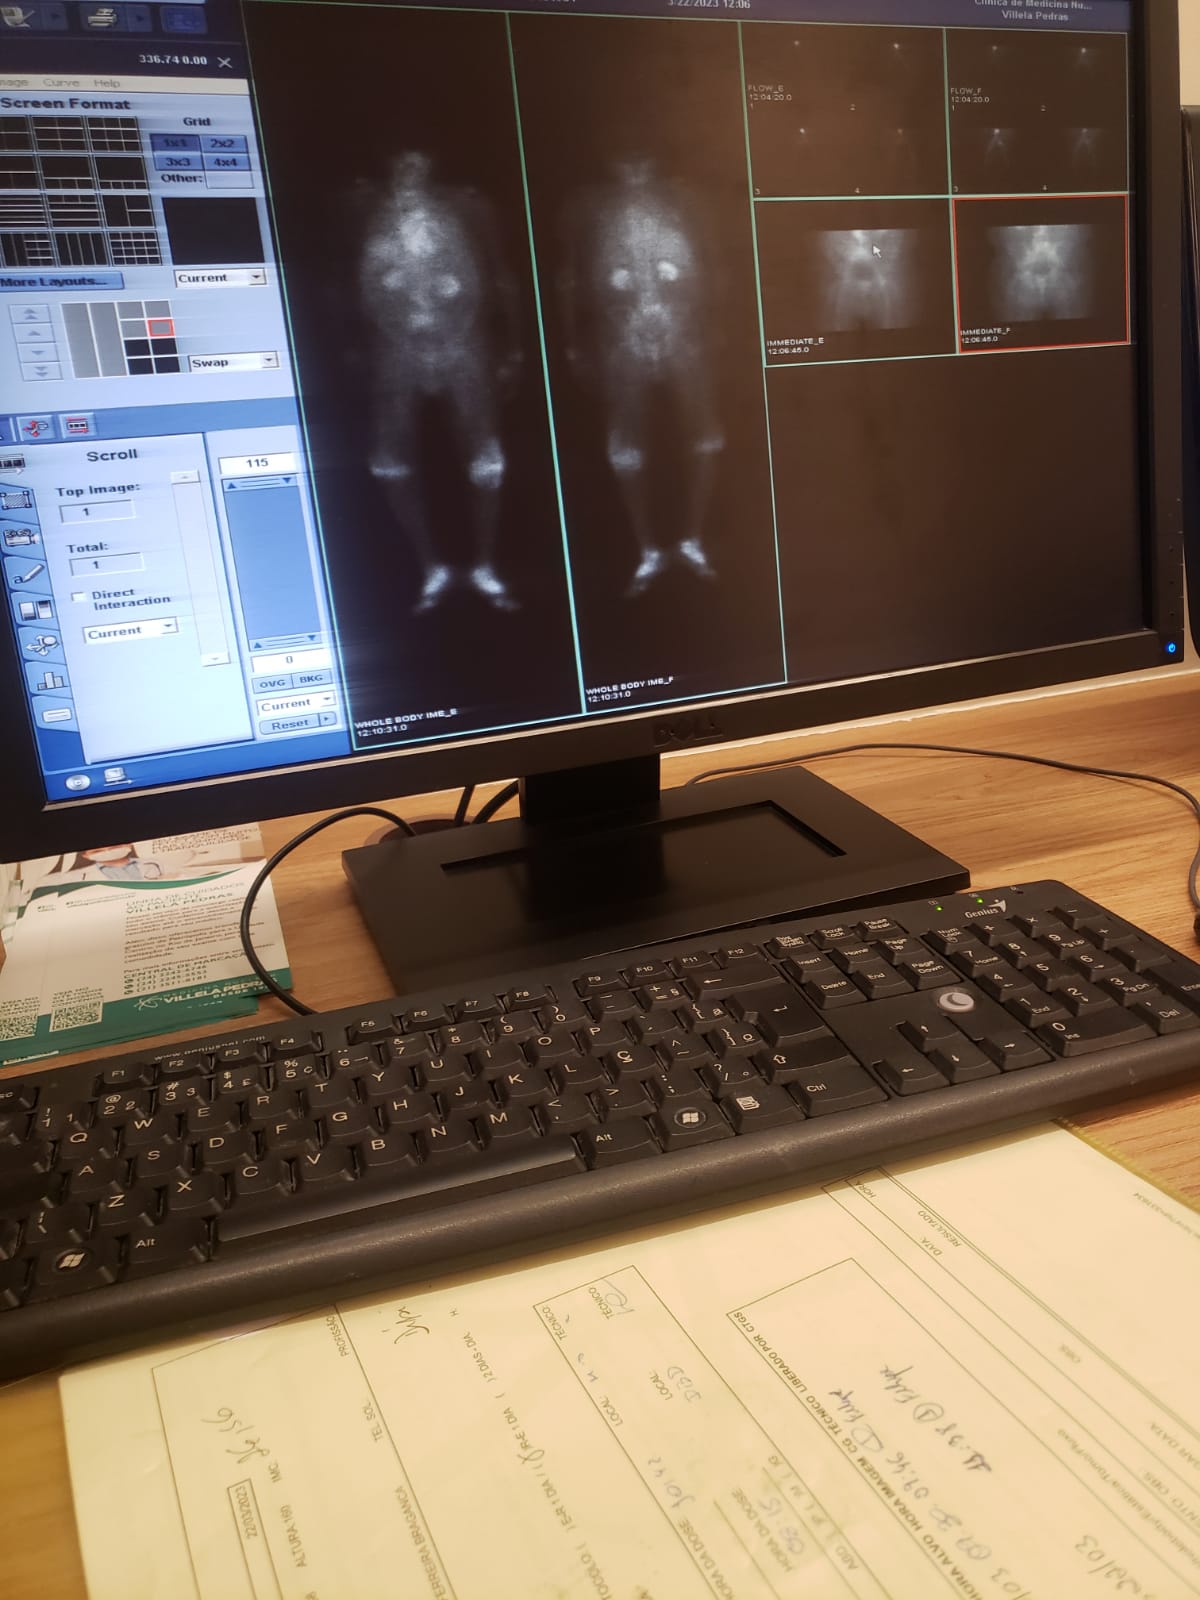

me chamo felipe, tenho 31 anos, trabalho na trabalho na área da saúde como cuidador no brasil, sou técnico de raio x e estudante de biomedicina no brasil